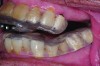

Accurate impressions of the upper and lower dentition are required for custom fabrication of a MAD. Because some appliances extend beyond the teeth, it is recommended that the impression capture at least 3-4 mm of soft tissue surrounding the teeth. The lower impression must capture the distal surfaces of the most distal teeth on both sides of the arch. The MAD must be fabricated to extend to include these surfaces; otherwise, diastemas may form with the adjacent mandibular teeth (Figure 2 through Figure 4).

Fig 2. Inadequate posterior extension of a MAD. The posterior extent of the MAD failed to capture the distal surfaces of the mandibular second molars. All third molars were absent.

Fig 3. Eight months later, diastemas had developed between the mandibular second and first molars.

Fig 4. The appliance was returned to the dental lab for correction of the distal extensions, using the original dental casts. The diastemas closed in response to the anteriorally directed force applied to the mandibular second molars (not shown).

Fig 2. Inadequate posterior extension of a MAD. The posterior extent of the MAD failed to capture the distal surfaces of the mandibular second molars. All third molars are absent.

Fig 3. Eight months later, diastemas have developed between the mandibular second and first molars.

Fig 4. The appliance is returned to the dental laboratory for correction of the distal extensions, using the original dental casts. The diastemas closed in response to the anteriorally directed force applied to the mandibular second molars (not shown).

Figure 3

Figure 4